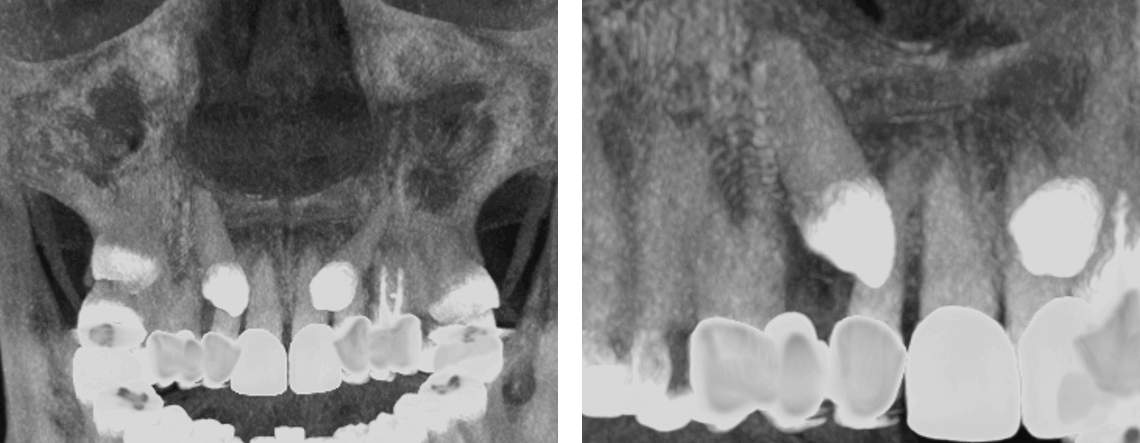

Fig.4

En la representación tridimensional (Fig.4) se observa la impactación del órgano dentario 13 y su relación con las estructuras vecinas.